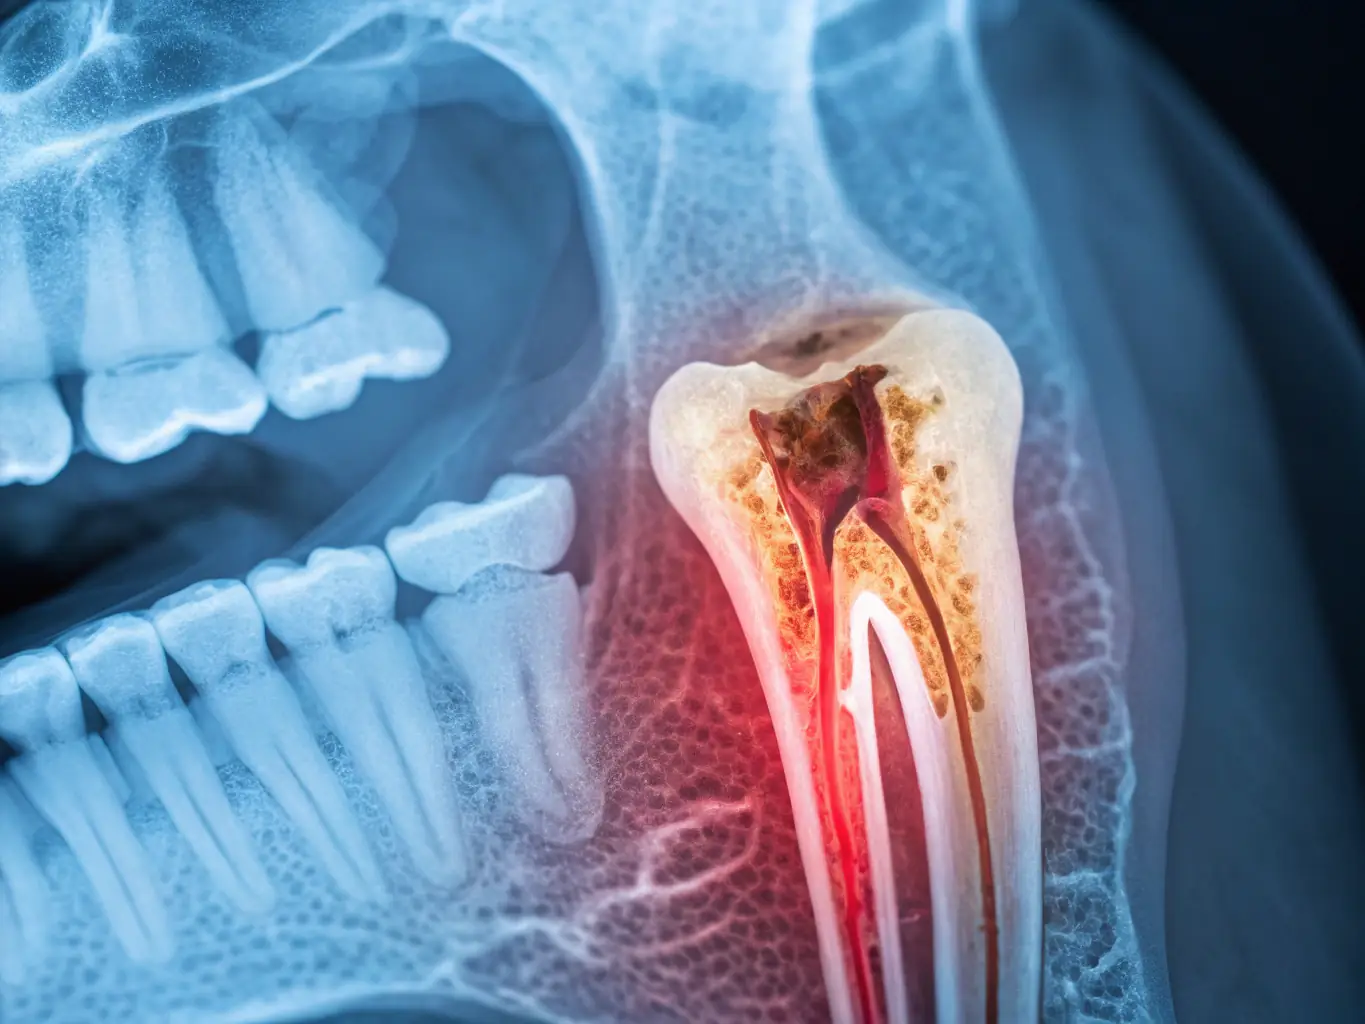

A close-up, detailed x-ray image showing impacted wisdom teeth pressing against the adjacent molars, causing visible crowding and potential damage. The image is professionally taken and highlights the need for extraction.

Preventing Future Dental Problems

Impacted wisdom teeth can lead to crowding, cysts, and damage to nearby teeth. Early removal prevents these issues, ensuring a healthier smile. Our team at Joshua Dental is here to help.

Avoiding Pain and Discomfort

Impacted or infected wisdom teeth can cause significant pain and discomfort. Removing them eliminates these issues, improving your quality of life. Joshua Dental offers sedation options for a comfortable experience.